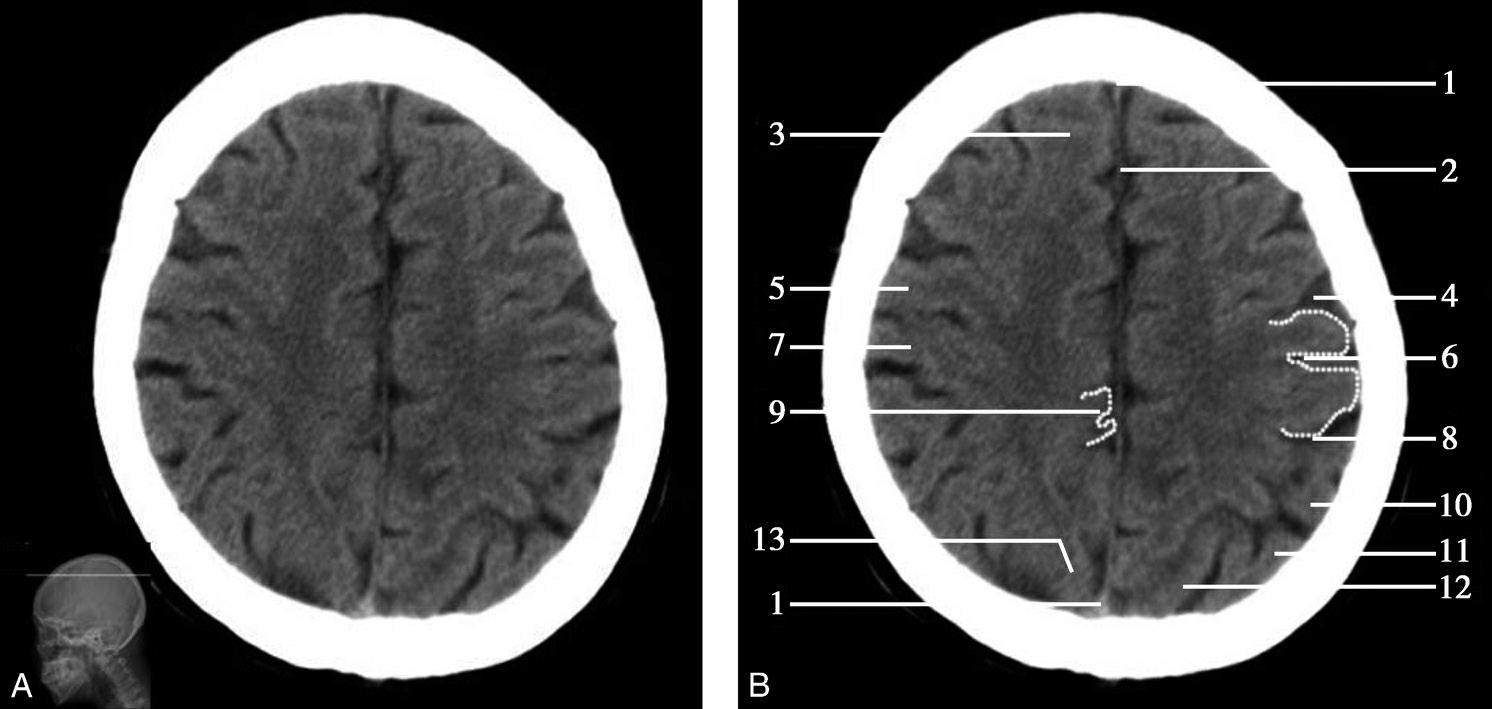

重要结构:中脑导水管、第三脑室、外侧裂池、岛叶、上矢状窦、四叠体池(图1-2-21~图1-2-23)。

图1-2-21 中脑导水管层面

A.横断面;B.横断面标注

1.额窦;2.上矢状窦;3.大脑镰;4.额叶;5.颞肌;6.外侧裂;7.岛叶;8.尾状核头;9.外囊;10.第三脑室;11.豆状核;12.颞叶;13.中脑;14.中脑导水管;15.环池;16.四叠体池;17.小脑上蚓部;18.枕叶